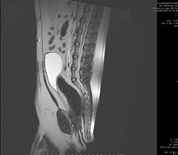

בדיקת MRI

בדיקת דימות תהודה מגנטית (Magnetic Resonance Imaging (MRI הינה אמצעי ההדמיה המתקדם ביותר להמחשת רקמות רכות בגוף, תוך שימוש בשדה מגנטי במקום בקרני רנטגן, ולכן נחשבת בטוחה מאוד.

MRI עמוד שדרה - פריצת דיסק, טראומות עמוד שדרה (למשל לאחר תאונת דרכים או נפילה מגובה), גידולים סרטניים, דלקת בנוזל חוט השדרה.

מחלות אורתופדיות- פתולוגיות בגידים, קרע ברצועה צולבת קדמית, פגיעה במניסקוס ועוד.